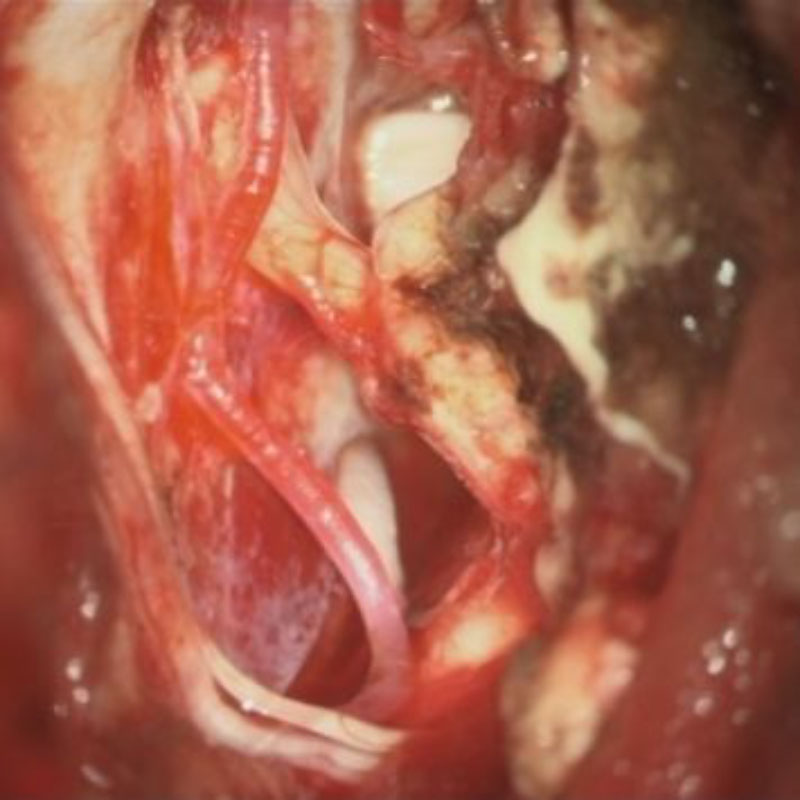

術中写真

摘出 中